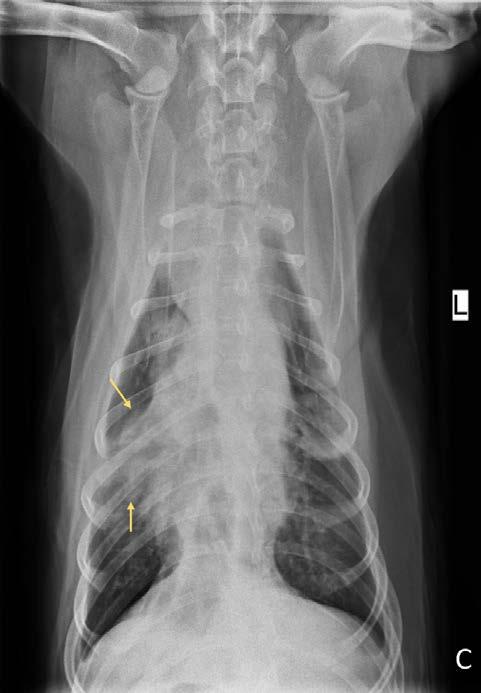

Se realiza la necropsia en la que se observa el corazón dentro del saco pericárdico con abundante líquido pericárdico. Se observa una gran masa redondeada de 7 x 5 x 3 cm en la base de la aorta, de consistencia firme, vascularizada, la cual al corte presenta vascularización y cavitaciones, áreas de hematoma y áreas de tejido graso y tejido fibroso. Se observa engrosamiento y degeneración de ambas válvulas atrioventriculares y, además, presencia de un nódulo en la válvula tricúspide de aspecto liso, color beige, no vascularizado de 1,5 cm. Se realizó en la toma y envío de muestras de las lesiones observadas en la base de corazón y tricúspide (Figs. 7, 8, 9 y 10). El análisis histopatológico de ambas lesiones confirma la sospecha diagnóstica de quemodectoma, siendo el nódulo tricúspide metástasis de la neoplasia principal en la base aórtica (Fig. 11), ya

Figura 7. Imagen de corazón evidenciando masa en base aórtica (flecha). Figura 8. Detalle de masa adherida a aorta. Masa esponjosa, cavitada, vascularizada, con áreas de necrosis y tejido adiposo. Figura 9. Detalle de masa tricúspide (flecha). Visión desde aurícula derecha. Figura 10. Detalle de masa tricúspide (flecha) adherida a las valvas. Vista gracias a la apertura completa del ventrículo derecho.

Figura 11. Vista histopatológica de tumor neuroendocrino: Se observa una proliferación de células poligonales formando nidos y paquetes y también áreas de empalizada alrededor de pequeños vasos sanguíneos. Las células muestran bordes indefinidos, citoplasma escaso a moderado eosinófilo finamente granular, núcleo redondo, cromatina granular y nucléolo variablemente presente, pequeño, redondo y basófilo. La anisocitosis y anisocariosis son moderadas.

que al examen microscópico en ambas localizaciones se observaron células de bordes indefinidos, citoplasma escaso a moderado eosinófilo finamente granular, núcleo redondo, cromatina granular y nucléolo variablemente presente, pequeño, redondo y basófilo. También se observó anisocitosis y anisocariosis moderadas. Se reconocieron mitosis en 10 campos de 40X a través de la autólisis en la muestra. Se diagnosticó así en la muestra de aorta y tejido adiposo de la base cardíaca un carcinoma neuroendocrino, consistente con quemodectoma, con invasión intravascular. En la muestra de la válvula tricúspide y miocardio de la pared ventricular derecha se diagnosticó metástasis valvular miocárdica de carcinoma neuroendocrino y degeneración mixomatosa de la válvula tricúspide, marcada, crónica y difusa (endocardiosis). Además, la lesión neoplásica en tricúspide presentaba carácter infiltrativo hacia el tejido miocárdico de la pared ventricular derecha y epicardio (Fig. 12).

Figura 12. Vista histopatológica de lesión tricúspide, infiltrando, expandiendo y obliterando la válvula tricúspide; en una de las secciones se observa un nódulo moderadamente delimitado, no encapsulado, expansivo y densamente celular que se extiende hacia la luz del ventrículo y atraviesa todo el miocardio hacia el tejido adiposo del epicardio. La masa muestra características similares a lo descrito para la proliferación previa, por lo que se considera metástasis de la primera.